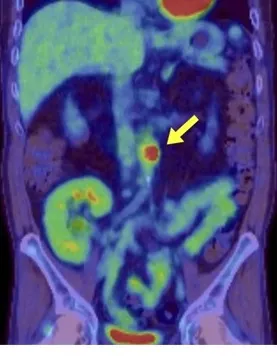

Hematúria e anormalidades em tomografia